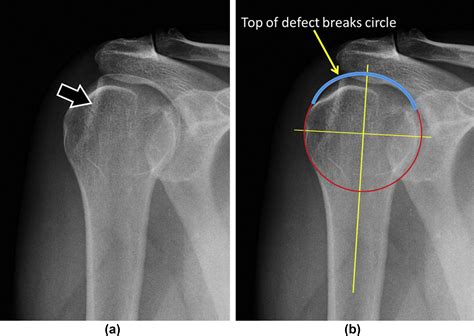

Diagram showing the shoulder joint and a Hills Sachs lesion on the humeral head

The shoulder is a ball-and-socket joint, designed for a vast range of motion. However, this flexibility comes at the cost of stability. When an anterior shoulder dislocation occurs, the humeral head is pushed forward and out of the socket. In many cases, the bone travels until it strikes the glenoid rim. Because the bone of the humeral head is relatively soft, the harder bone of the glenoid rim acts like a stamp, creating a “divot” or notch in the humeral head.

This indentation is the Hills Sachs lesion. It is important to note that these lesions are highly prevalent in patients who experience recurrent shoulder instability. Once the bone has been dented, the "locking" mechanism of the shoulder is compromised, making it easier for the joint to dislocate again in the future. This creates a cycle of instability that often requires medical intervention to correct.